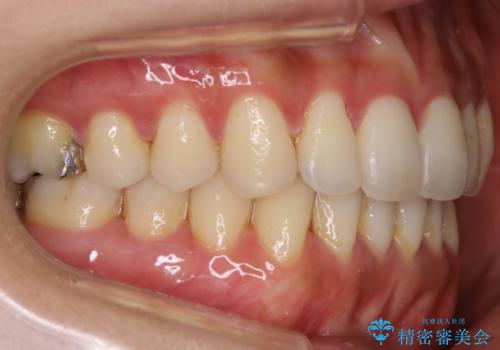

- 歯のガタつきによる見栄えや清掃困難を主訴にご来院されました。

左側の噛み合わせは上の歯が前方に寄ってきてしまっていることが原因のズレがありました。

ガタつき自体は歯列の幅の拡大やディスキング(IPR)でほとんど解消可能でしたが、噛み合わせのズレは歯の移動が必要だったため、左上にマイクロインプラントを使用し噛み合わせの改善とガタつきの解消を同時に進めるという方針をとりました。